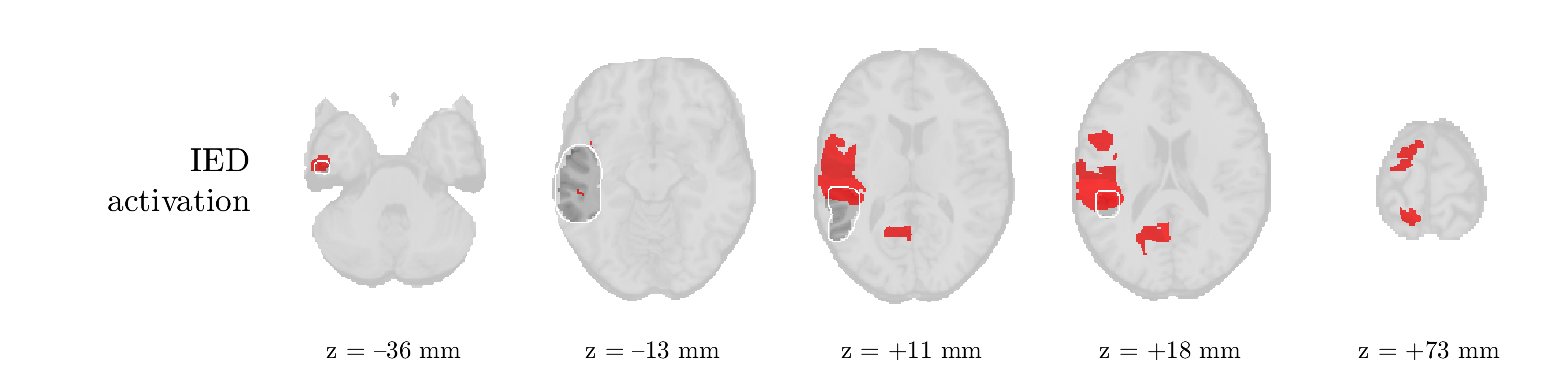

Patient 2

We analyze the solution with sources, and show the results in Figure 3 and 4. As for patient 1, we found a source which is strongly correlated to the MWF envelope, and which had a mostly low-frequency behavior characteristic for spikes. The topography is mostly uninformative, and does not clearly correspond to the patient’s clinical data. The third source is mostly present at both sides of the head, is very sparsely active in time, and has a high-frequency content: this is most likely an artifact due to the neck muscles. Again, there is one of the highest-entropy HRFs which belongs to a ROI in the IOZ. Now, the waveform is clearly resolved from the other HRFs, through the strong initial dip (before 0 seconds). Such a dip is sometimes observed in HRFs, but its underlying physiological mechanism is not yet fully understood. It is possible that this dip reflects altered vascular autoregulation near the IOZ (cfr. the explanation in the Section 1 of the main text), or a rapid depletion in oxygen due to IED generation (before the IED becomes visible on the EEG). Figure 4 furthermore shows that the IED-related component is significantly active in parts of the IOZ, and deactive in others. As mentioned earlier, this deactivation may or may not be due to errors in sign correction. Interestingly, the ROI with the high alteration in neurovascular coupling is distinct from both the activated and deactivated ROIs.